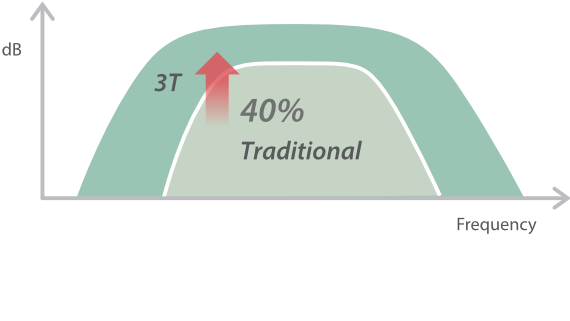

Sobre la base de un profundo conocimiento de las necesidades del cliente, el DC-60?ECHO con X-Insight estå dise?ado para brindar alta eficiencia con imågenes precisas, lo que se ve potenciado con eXpress Clarity (claridad exprés), eXceptional Intelligence (inteligencia excepcional) y eXceeding Experience (experiencia extraordinaria).